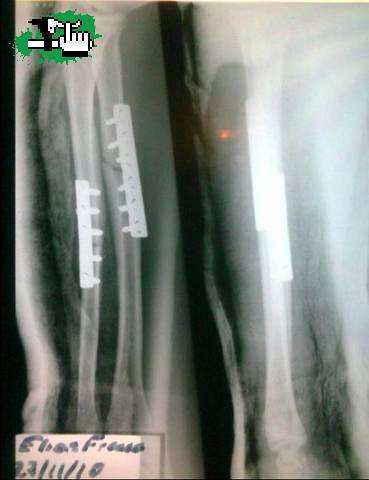

y bueno asi quedo mi brasito despues de un 360 gap

bastante fallido jajaja tengo media ferreteria

ahi.......... pero bueno ya volvi a andar asique esta

todo mas que bien!! :D